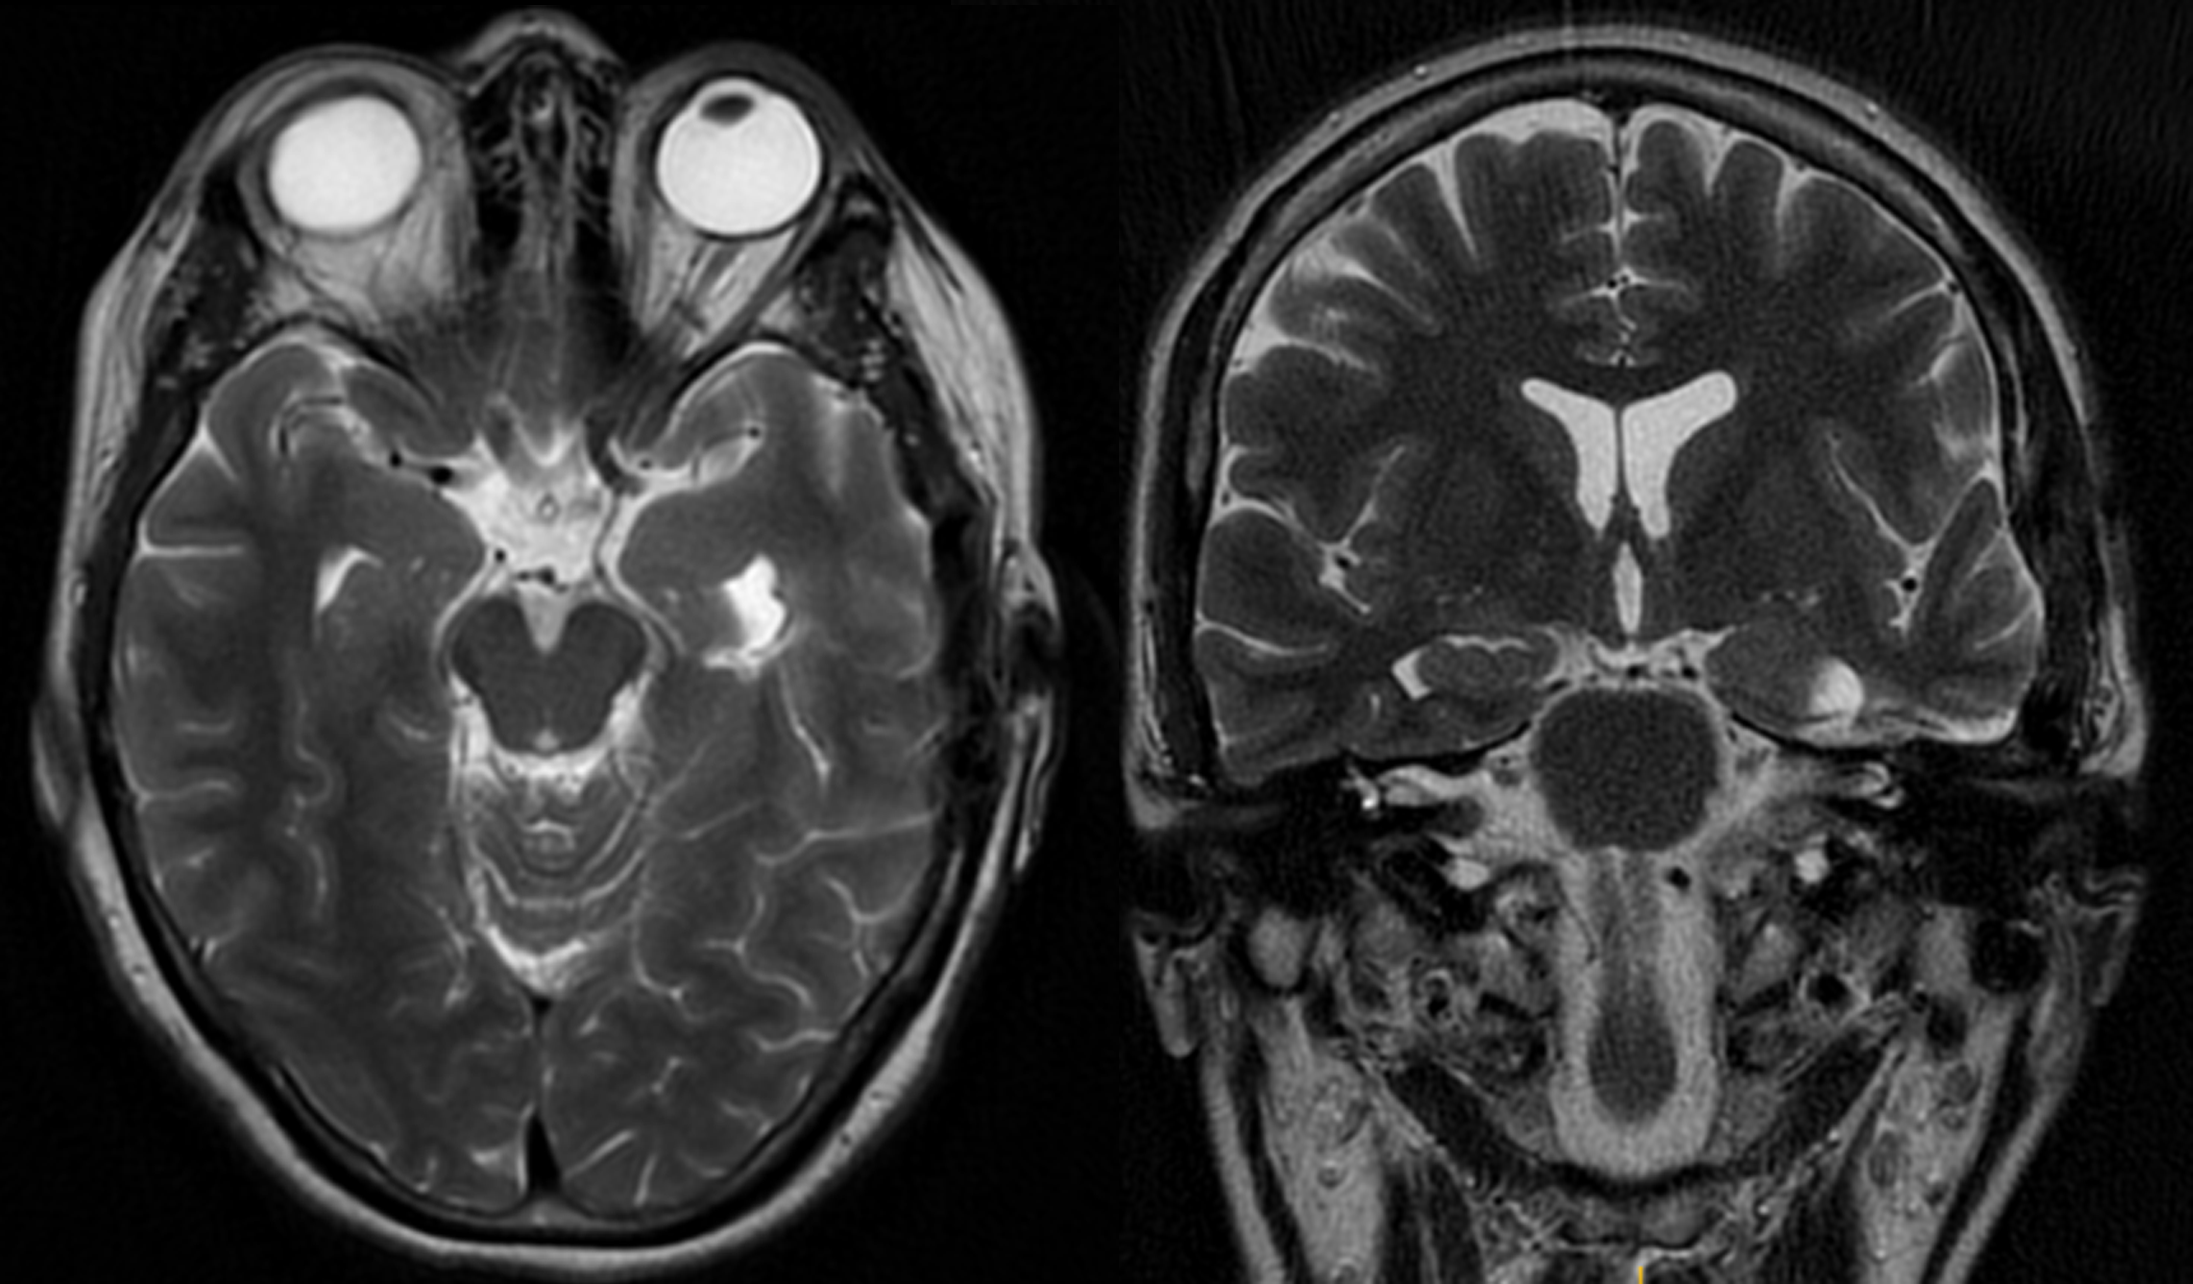

CASO EJEMPLO 1: CAVERNOMA INCIDENTAL LENTICULAR ANTERIOR DERECHO.

Fig 1: 2020: Mujer, 33 años, cavernoma incidental no complicado.

Fig 2: 2021: Persiste asintomática con hematoma intracapsular en RMN control.

Fig 3: 2021: RMN postop. de exéresis por vía transilviana trans-surco circular anterior de la ínsula.